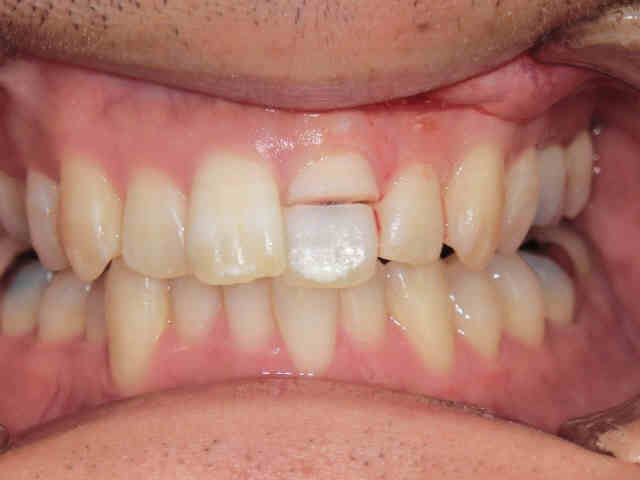

上記写真は、治療前の状態です。